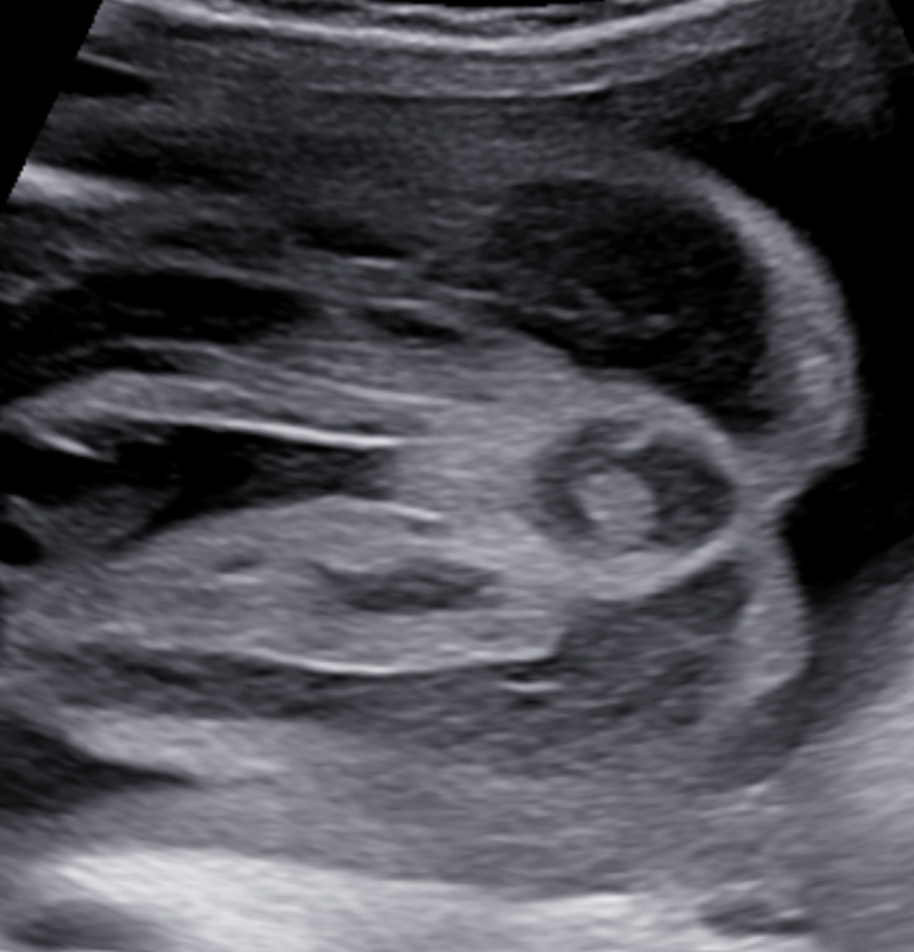

• Target sign (dấu hiệu trực tiếp)

• Mô tả: Trung tâm tăng âm (niêm mạc), bao quanh bởi cơ vòng giảm âm (cơ vòng hậu môn

• Ưu điểm: Dễ thực hiện, được nghiên cứu kĩ

• Nhược điểm:

• Không phải lúc nào cũng thấy (nhất là những trường hợp tắc thấp)

• Phụ thuộc tuổi thai (tốt nhất 28–32 tuần)

• Có thể: không thấy trong điều kiện kỹ thuật kém (thành bụng dày, ối ít

Hình 3: dấu target điển hình ở thai bình thường

Hình 4: dấu target không điển hình ở bệnh nhân không lỗ hậu môn